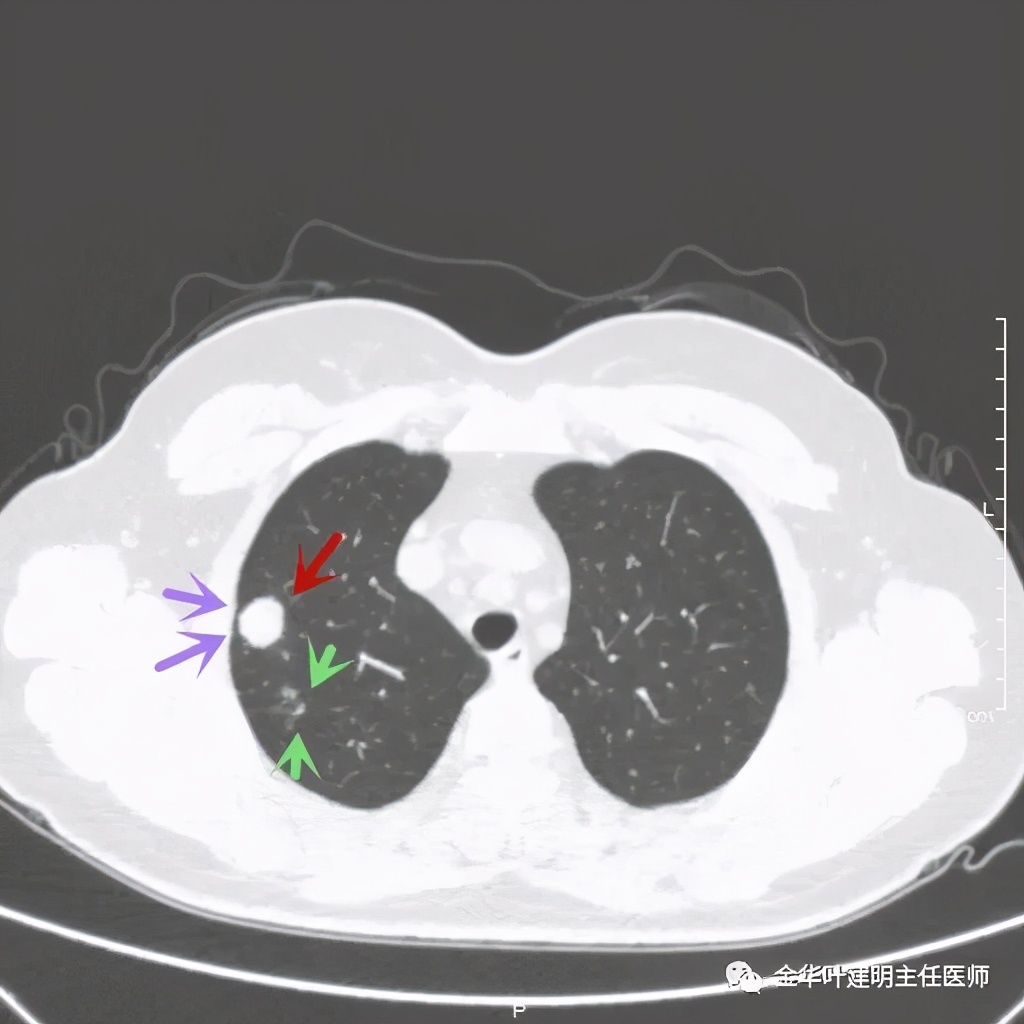

绿色箭头示病粉旁边有卫星灶,而且密度都高,主病灶也是实性

病灶边散在多发微小实性与似磨玻璃的微小结节

病灶附近不清爽

距主病灶一段距离的地方,也有小的实性微结节

总体感觉病灶较大,但边缘过于光滑,缺乏收缩力,没有毛刺征、分叶征、胸膜凹陷征;旁边却有多发微小实性或似磨玻璃结节,周围不清爽。让人感觉非肿瘤性质,炎性可能性大些,比如结核等。那么纵隔窗又是如何呢?我们选两个层面来看: